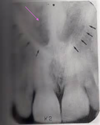

What two bone structures are represented in this picture?

Alveolar Bone & Alveolar Crest

The radiopaque line surrounding the tooth in this picture is called what?

Lamina Dura

The radiolucent area in the center of the tooth is called what? (the green arrow)

Pulp Chamber

What is letter A in the picture pointing out?

Enamel

What is letter B pointing out in the picture?

Dentin